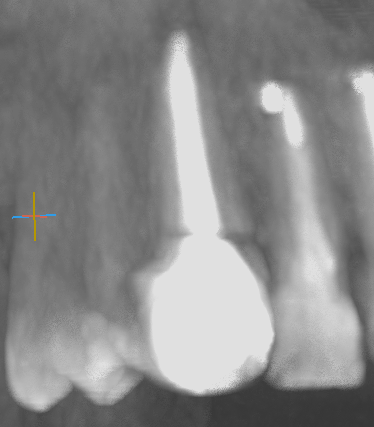

Делали 13 зуб, хронический периодонтит. Дистальная стенка ушла под десну. Делали эндо, врач почему-то решила сразу пломбировать каналы и сделать реставрацию композитом. Ничего не сказала, но на ОПТГ и КТ вот такая картина. Как будто трещина, да? Включая и материал в канале тоже - фрагментация какая-то...

Перелом?

Спасибо. Посмотрим что на следующем снимке будет. Так-то боли и подвижности нет. Первый раз такое на КТ вижу у себя.